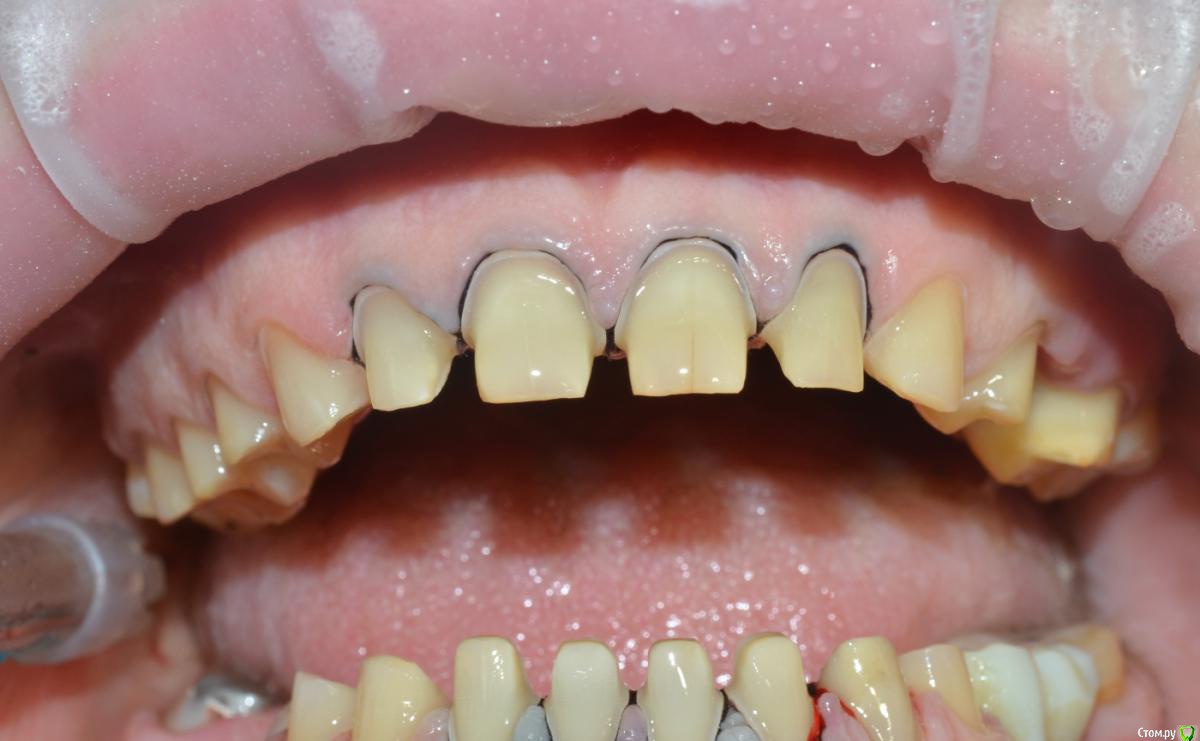

NazranDantist Опубликовано 21 мая, 2015 Поделиться Опубликовано 21 мая, 2015 (изменено) Коллеги поделитесь опытом. Какой план лечения предложить пациентке. Планируется тотальная работа что-нибудь из безметаловой технологии (E-max или претау, еще обдумываем). Вопрос, как выровнять оклюзионную плоскость, нужно ли прибегать к помощи ортодонта? Больше всего интересует первый сегмент, особенно зуб 15, висит слишком сильно. Или все таки стараться выйти из положения керамикой плюс хирургическое удлинение? Изменено 21 мая, 2015 пользователем NazranDantist Ссылка на комментарий

NazranDantist Опубликовано 4 сентября, 2015 Автор Поделиться Опубликовано 4 сентября, 2015 Продолжение кейса. Работа еще не закончена, зуб 25, 35, 36 - аббатменты на подходе, поэтому решили сделать после отпуска пациентки. Фото протокол не соблюдал, курс рубля прыгал, торопился в обменник . Вся работа - имакс на Цереке с редуцированием, фиксация - фронт на чойс, боковые - У-200. Ссылка на комментарий